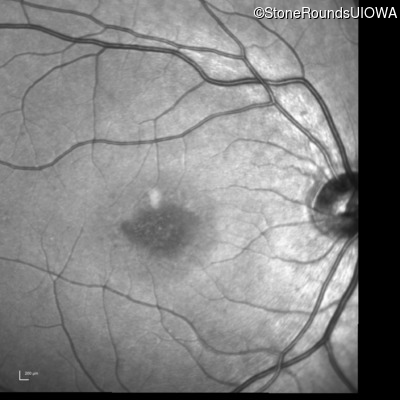

Infrared Fundus Photograph - Right - 20/80 -1

Exemplar